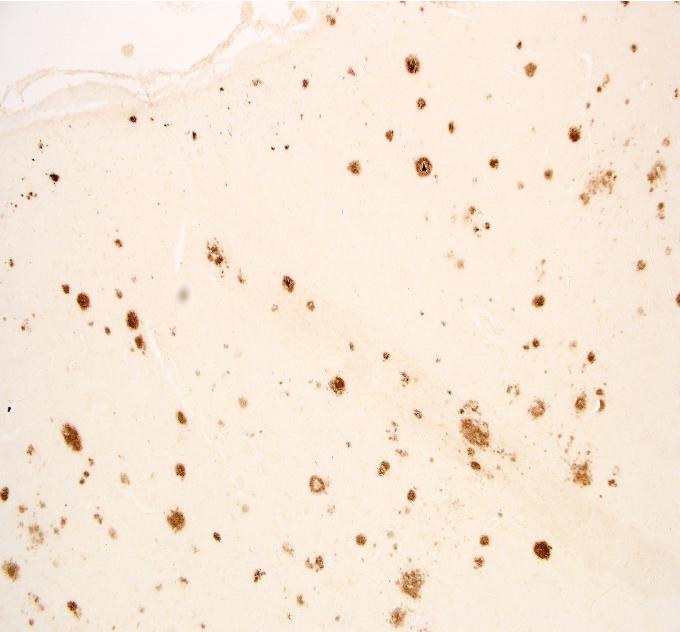

image: The study showed the severity of sleep apnea was linked with a corresponding build-up of amyloid plaques (seen here as brown patches in the brain tissue).

While the cause of Alzheimer's disease remains a mystery, amyloid plaques that are toxic to brain cells are known indicators of the disease.

The new research showed these plaques start in the same place and spread in the same way in the brains of people with obstructive sleep apnea, as in those with Alzheimer's.

Significantly, the severity of sleep apnea was linked with a corresponding build-up of amyloid plaques.

While the study found both plaques and tangles in the brains of people with sleep apnea, the plaques showed a stronger association with severe sleep apnea.